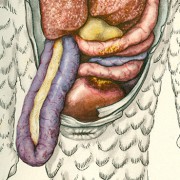

Lilly Ebstein Lowenstein (1897-1966) led a life between science and art, drawing and taking photographs in the fields of Medicine and Zoology. In her work, Lilly combined her technical knowledge of photography and drawing, the study of the sciences and a remarkable talent for aesthetics. She was born in Germany and studied at the Lette-Verein School in Berlin from 1911 to 1914. In 1925, she immigrated with her husband and two children to São Paulo. In 1926, she became an illustrator and photomicrographer at the Illustration and Photography Department at the School of Medicine (USP, as of 1934), which she headed for thirty years after 1932. Lilly collaborated at Instituto Biológico de Defesa Agrícola e Animal (the Biological Institute for the Defense of Agriculture and Animals), from 1930 to 1935, namely in the Avian Pathology Department. A life with art dedicated to the research and dissemination of science.